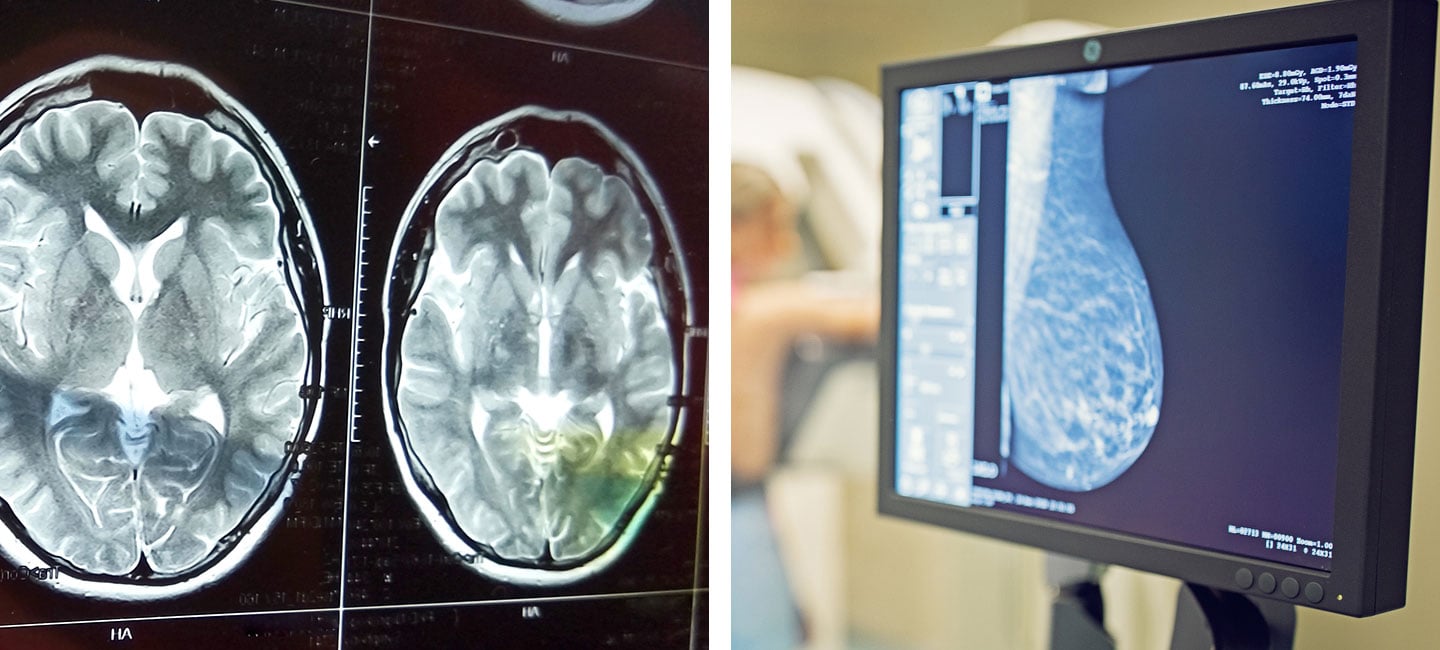

Moffitt Launches Innovative Trial for Brain-Metastatic Breast Cancer

Moffitt Cancer Center is preparing to launch a new, innovative clinical trial for brain-metastatic breast cancer patients, thanks to a new grant from the Department of Defense (DoD). The DoD awarded the cancer center a four-year, $8.3 million Breakthrough Award to fund a phase 2 clinical trial led by Brian Czerniecki, M.D., Ph.D., chair of Moffitt’s Breast Cancer Oncology Department.

Roughly 10% to 15% of women with Stage IV breast cancer develop brain metastases, and there are very few treatment options for this group. The trial will begin first in patients with localized brain-metastatic breast cancer (BMBC) that is not widely spread, and then expand to include patients with disseminated, leptomeningeal BMBC.